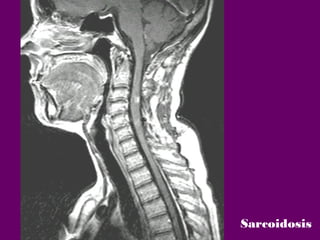

Sarcoidosis